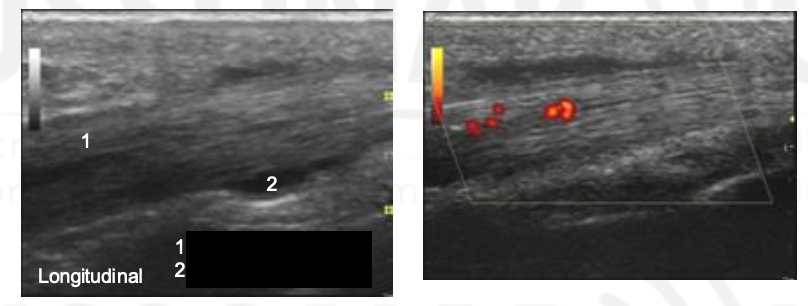

Name 1 and 2.

Tendon

Tendon sheath effusion

Note that the tenosynovial effusion is anechoic and

compressible, and on both sides of the tendon. Compare

how the deep portion of the tenosynovial fluid is abutting

the tendon and how synovial fluid from the PIP joint

would be abutting the bone.